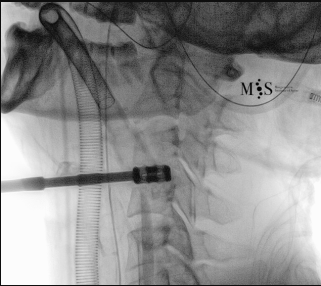

Images showing the endoscopic placement of a cage into a cervical disk

Animated image showing the endoscopic insertion of an intervertebral cage into a cervical disk.

Note the distraction of the disk space during as the cage is inserted.

Endoscopic ACDF starts with an endoscopic discectomy to decompress neural structures, like the spinal cord, and prepare the disk for the cage placement. Once the interbody cervical disk has been prepared, the an interbody device is percutaneously placed into the disk. This device can either be a titanium interbody cage to achieve vertebral fusion or a disk prothesis that allows to restore movement in the cervical spine. The placement of the device is done unter x-ray fluoroscopic control and direct endoscopic vision, see the animation on the figure at the right side of this page.